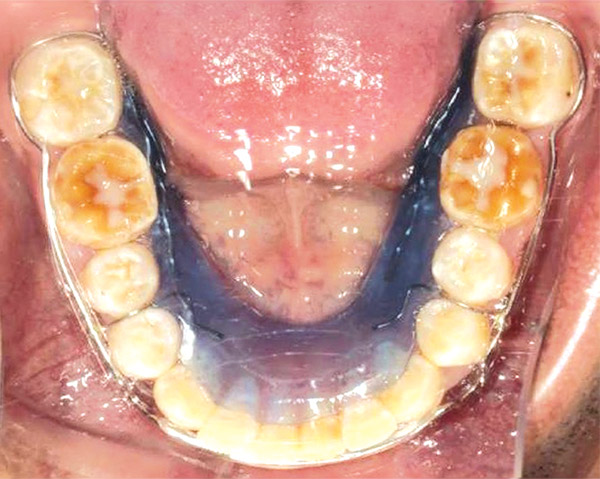

Estudios de progreso

Se observa en las fotografías intraorales la mecánica utilizada con los brackets y al paciente con mejor alineación y nivelación dental (Figura 12-14).

Respecto a las formas de arco superior e inferior que eran cuadradas en esta fase ya son ovales (Figura 15 y 16).

Figura 15. Oclusal superior.

Figura 16. Inferior.